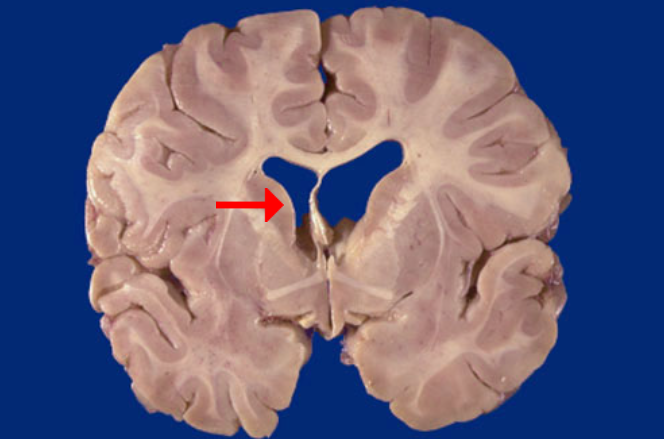

Label this brain structure

Caudate nucleus